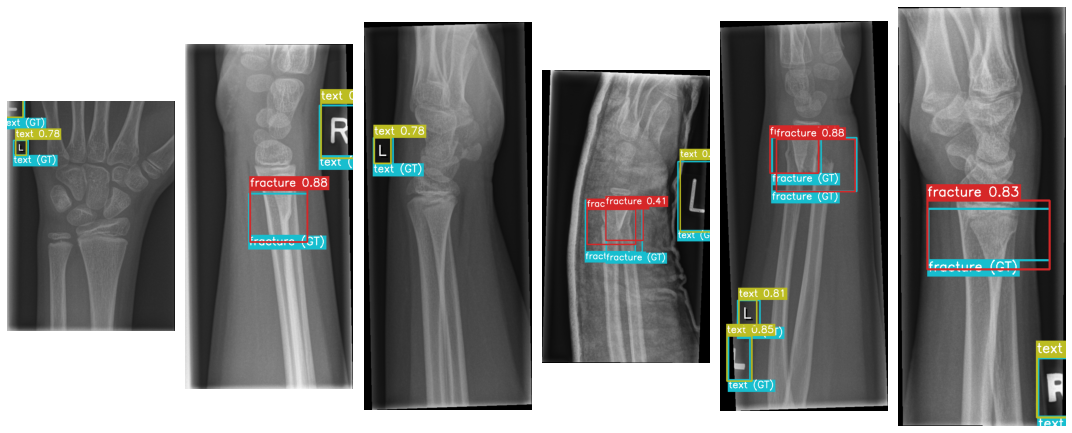

Fig1: few random testing images visualization within their realive ground-truth and the predicted labels with their confidence score by the trained YOLOv7-p6 model.

Fig1: few random testing images visualization within their realive ground-truth and the predicted labels with their confidence score by the trained YOLOv7-p6 model.